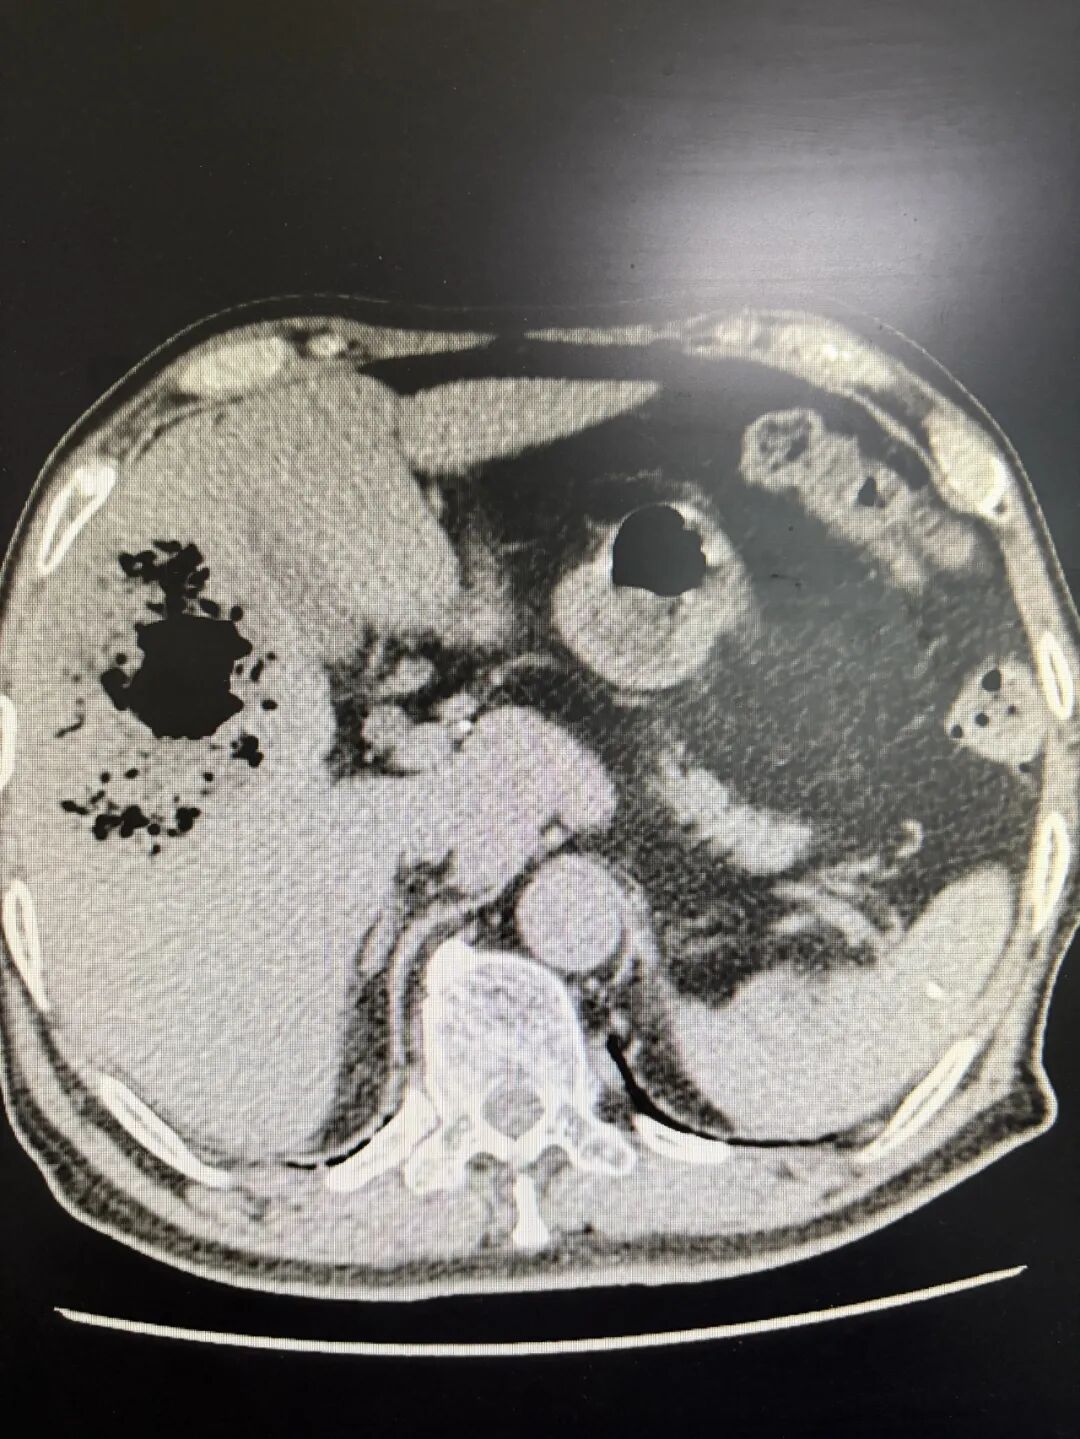

术前患者CT显示图

该患者年龄高达76岁,且既往有高血压、糖尿病病史多年,肺功能较差,加上脓毒血症的影响,极大增加了手术和麻醉难度。麻醉医师苏日娜精心配合,为手术顺利进行提供了重要保障。术中探查可见肝右叶包膜破裂出血并伴有脓液流出,与术前判断完全一致。